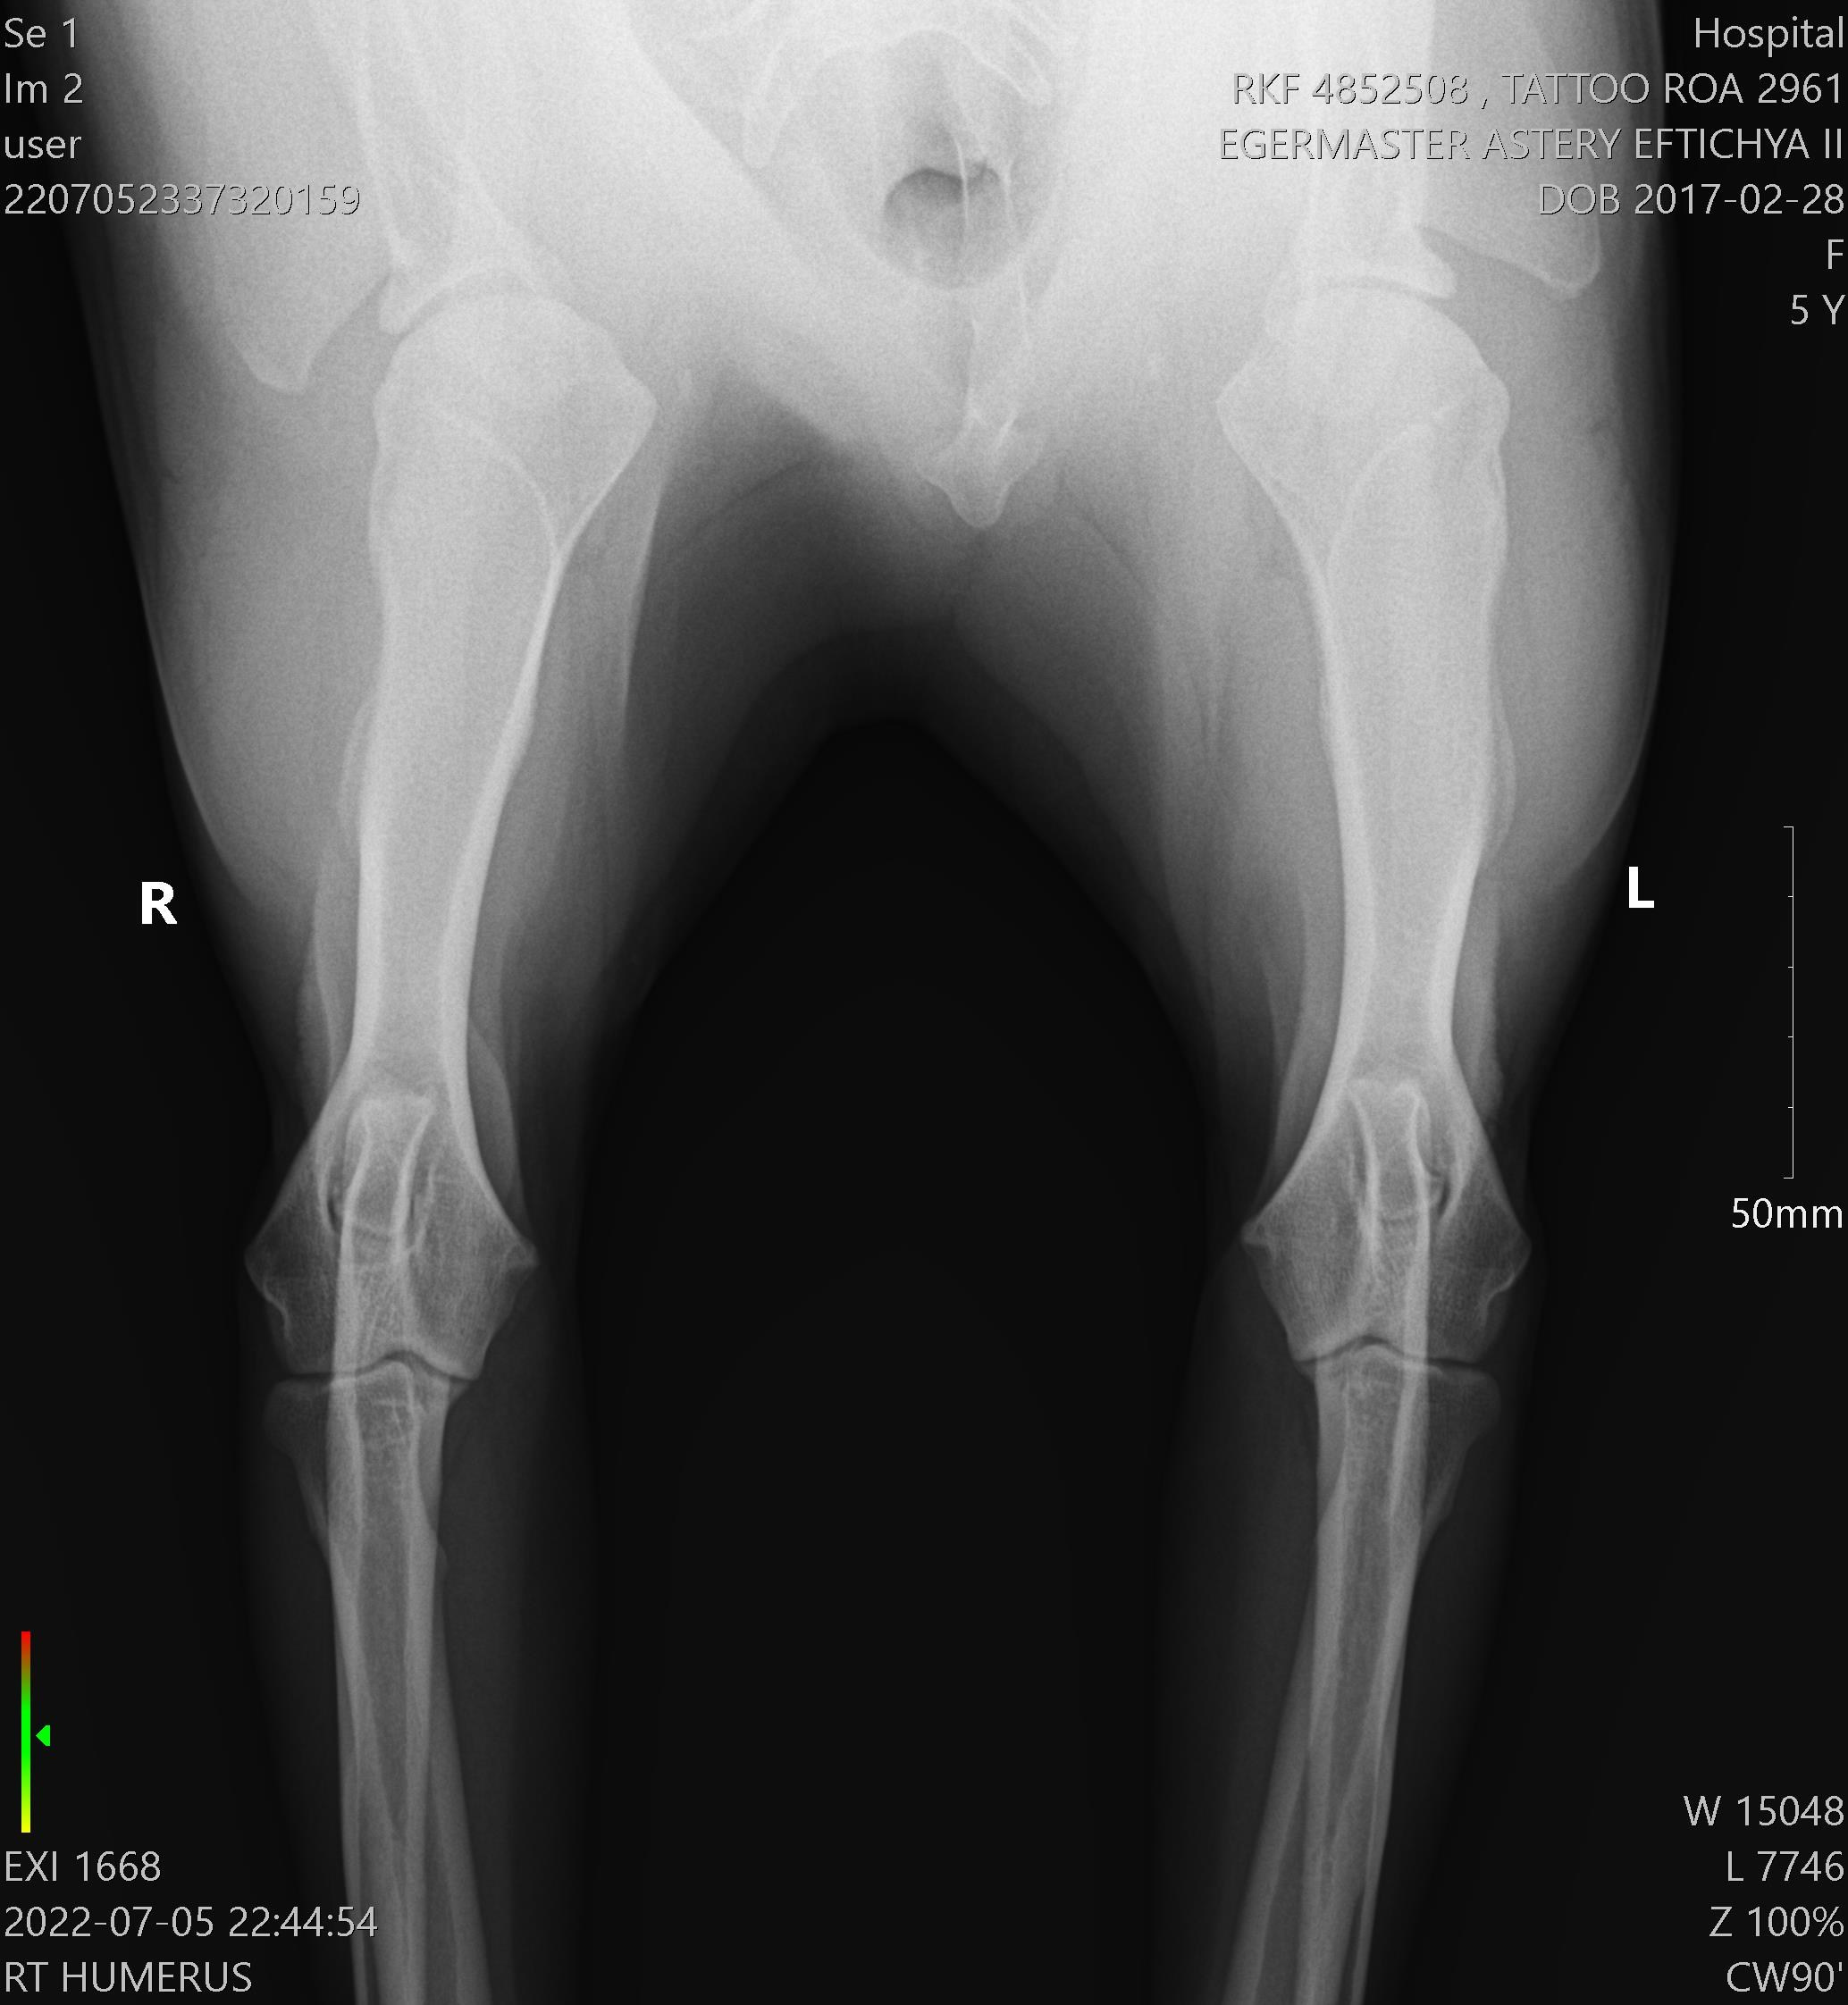

Егермастер Астери Эфтихия ll